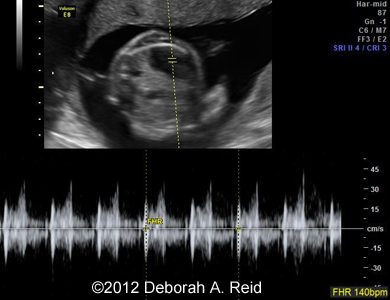

Ultrasound showed left-sided congenital diaphragmatic hernia with mild polyhydramnios.

The left-sided congenital diaphragmatic hernia contained a large portion of the bowel, spleen, stomach and the tip of the left lobe of the liver. In addition to the congenital diaphragmatic hernia, a sub-diaphragmatic sequestration was also noted which was confirmed by MRI.

Figure 1-10: The left-sided congenital diaphragmatic hernia contained a large portion of the bowel, spleen, stomach and the tip of the left lobe of the liver